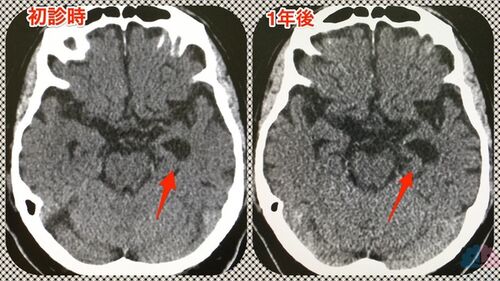

【症例報告】認知症になっていくか分からない曖昧な状態を、曖昧なまま経過観察していく難しさ。

今回は、通院から1年ちょっとで来院が途絶えてしまった方を紹介する。 ADLは自立しているが、特に強い病識を持っているわけではないMMさん。ただし、奥さんは今後について漠然とした不安を感じていた。 奥さんの想いにMMさんが引きずられる形で通院が始まったが、結…